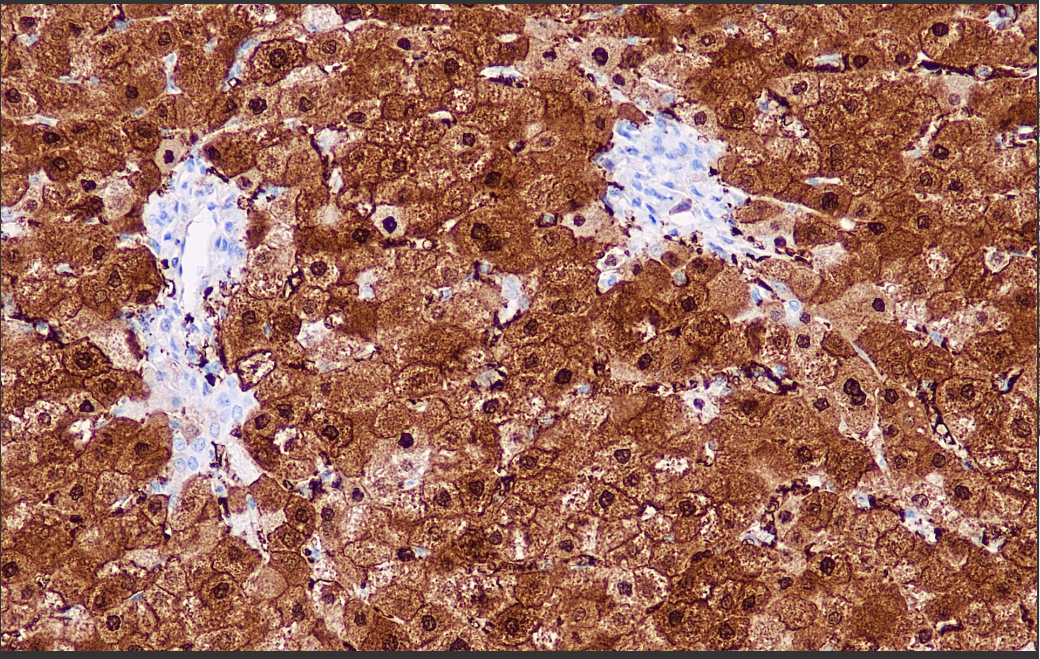

Positive control: Liver

Arginase-1, a key enzyme of the urea cycle, is expressed with high specificity in hepatocytes of normal liver tissues and is not expressed by bile duct epithelial cells, hepatic sinusoidal endothelial cells, blastic cells and vascular endothelial cells. Recent studies have shown that Arginase-1 is expressed in both normal and malignant liver tissues, especially in well-differentiated and moderately differentiated hepatocellular carcinomas (HCCs) with expression rates as high as 100% and 92%, and low in poorly differentiated hepatocellular carcinomas (LHCs). The combination of antibodies CD10, pCEA, AFP, HepPar-1, glypican-3, and A rginase-1 is of great significance in the study of benign liver lesions and well-differentiated hepatocellular carcinomas, poorly differentiated hepatocellular carcinomas, and metastatic tumors.

Arginase-1 Antibody Reagent binds specifically to Arginase-1 molecular antigen. Immunohistochemistry kits containing Arginase-1 Antibody Reagent are suitable for the precise diagnosis of benign liver lesions and well-differentiated hepatocellular carcinoma, poorly differentiated hepatocellular carcinoma and metastatic tumors.